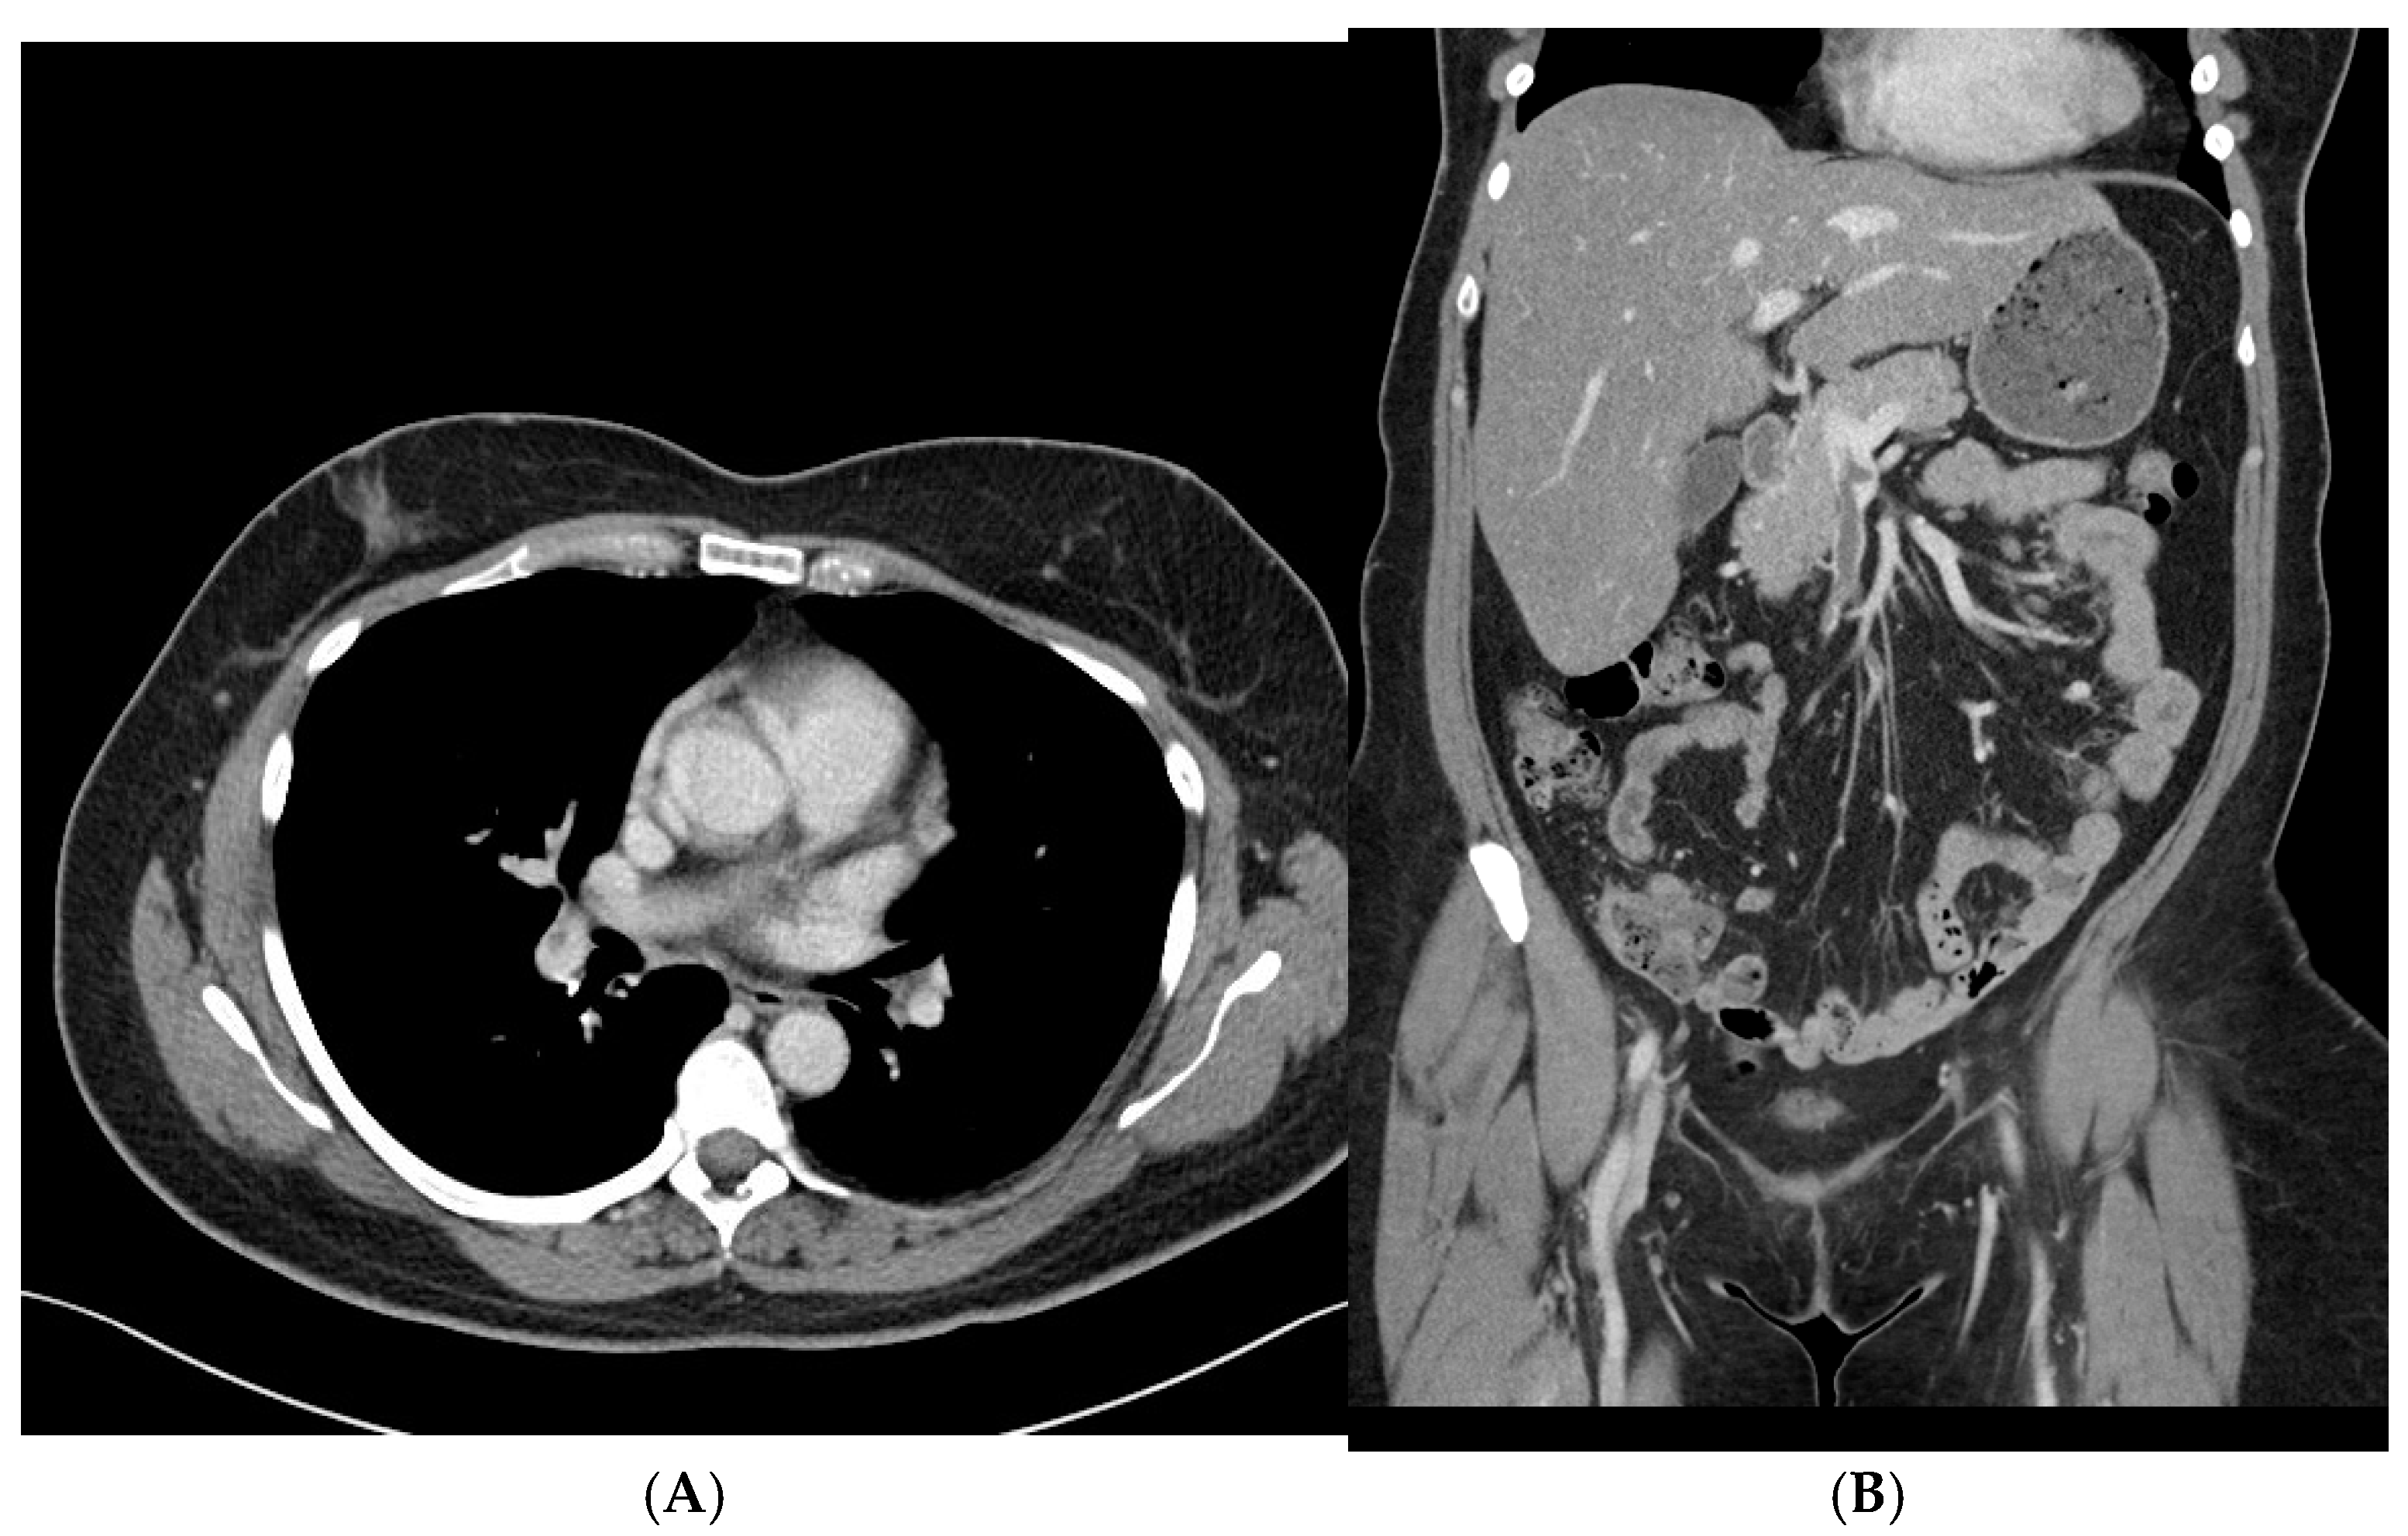

By hospital day 3, repeat brain CT and CT venogram showed that the intraparenchymal hemorrhage and venous sinus thrombosis remained stable, with no new areas of bleeding or clot extension. On hospital day 6, a CT scan of the chest, abdomen, and pelvis was obtained to evaluate for an underlying malignancy or other prothrombotic conditions. Imaging revealed a non-occlusive thrombus in the right main portal vein and superior mesenteric vein, as well as multiple non-occlusive emboli in the right superior and inferior pulmonary arteries. There was no evidence of right ventricular strain or malignancy. Given that these thrombi were identified after heparin cessation and the initiation of bivalirudin, it is possible they were already present before the transition in anticoagulation therapy, further supporting the underlying prothrombotic state associated with spontaneous HIT (Figure 2A,B).

Figure 2. (A,B) Contrast-enhanced CT imaging shows non-occlusive thrombi in the portal and superior mesenteric veins, along with multiple non-occlusive emboli in the pulmonary arteries.